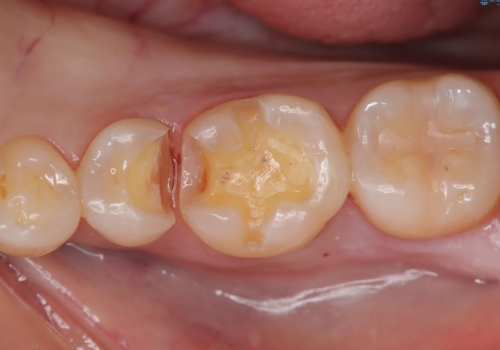

- 虫歯が複数個所あり、来院回数を抑えて治療をしたいという患者様でした。当院では光学スキャナ・ミリングマシンを設置しておりますので、1日でセラミック修復治療を完了させました。術後も良好な経過をたどっています。

メタル修復物の場合X線を通さない性質があり、レントゲン写真を撮るとメタルの部分が真っ白に写ってしまうため、詰め物の下の虫歯が分かりにくくなってしまうというデメリットがあります。これに対し、今回の即日セラミック修復に使用したMarkⅡという材料は、レントゲン写真からもわかる通り歯の一番外側の部分(エナメル質)と同程度のX線透過性を持ちます。そのため装着後も定期的なメンテナンスにより虫歯の再発を早期に発見できるメリットがあります。